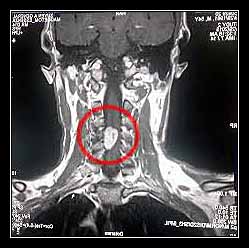

- Chụp cột sống: CT, RMI, siêu âm màu;

Để tìm nguyên nhân cần phải chụp scane, cộng hưởng từ, siêu âm màu hệ mạch, chọc ống sống nếu cần.